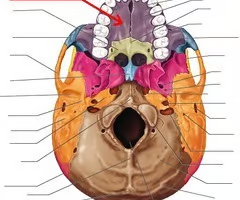

Carotid canal (for internal carotid artery)

Palatine process of maxilla (helps form hard palate with palatine bones)

Palatine bones

Vomer

Vomer

Occipital condyles (articulates with superior articular surfaces of atlas)

Foramen magnum (“big hole” for the spinal cord)